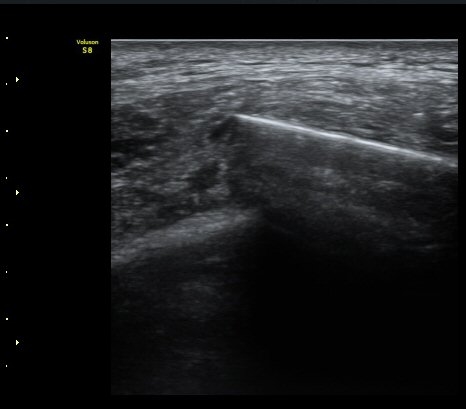

±¤¹è±Ù ½ÉºÎ¿¡ °¥ºñ»À»çÀ̱ÙÀÌ °üÂûµÇ°í °¥ºñ»À»çÀٰ̱ú Æó»çÀÌ¿¡ ¼ö¾×Àú·ù°¡

°üÂûµÊ(intercostal muscle deep to latissimus dorsi, fluid accumulation between intercostal muscle and lung)   »çÁø 4